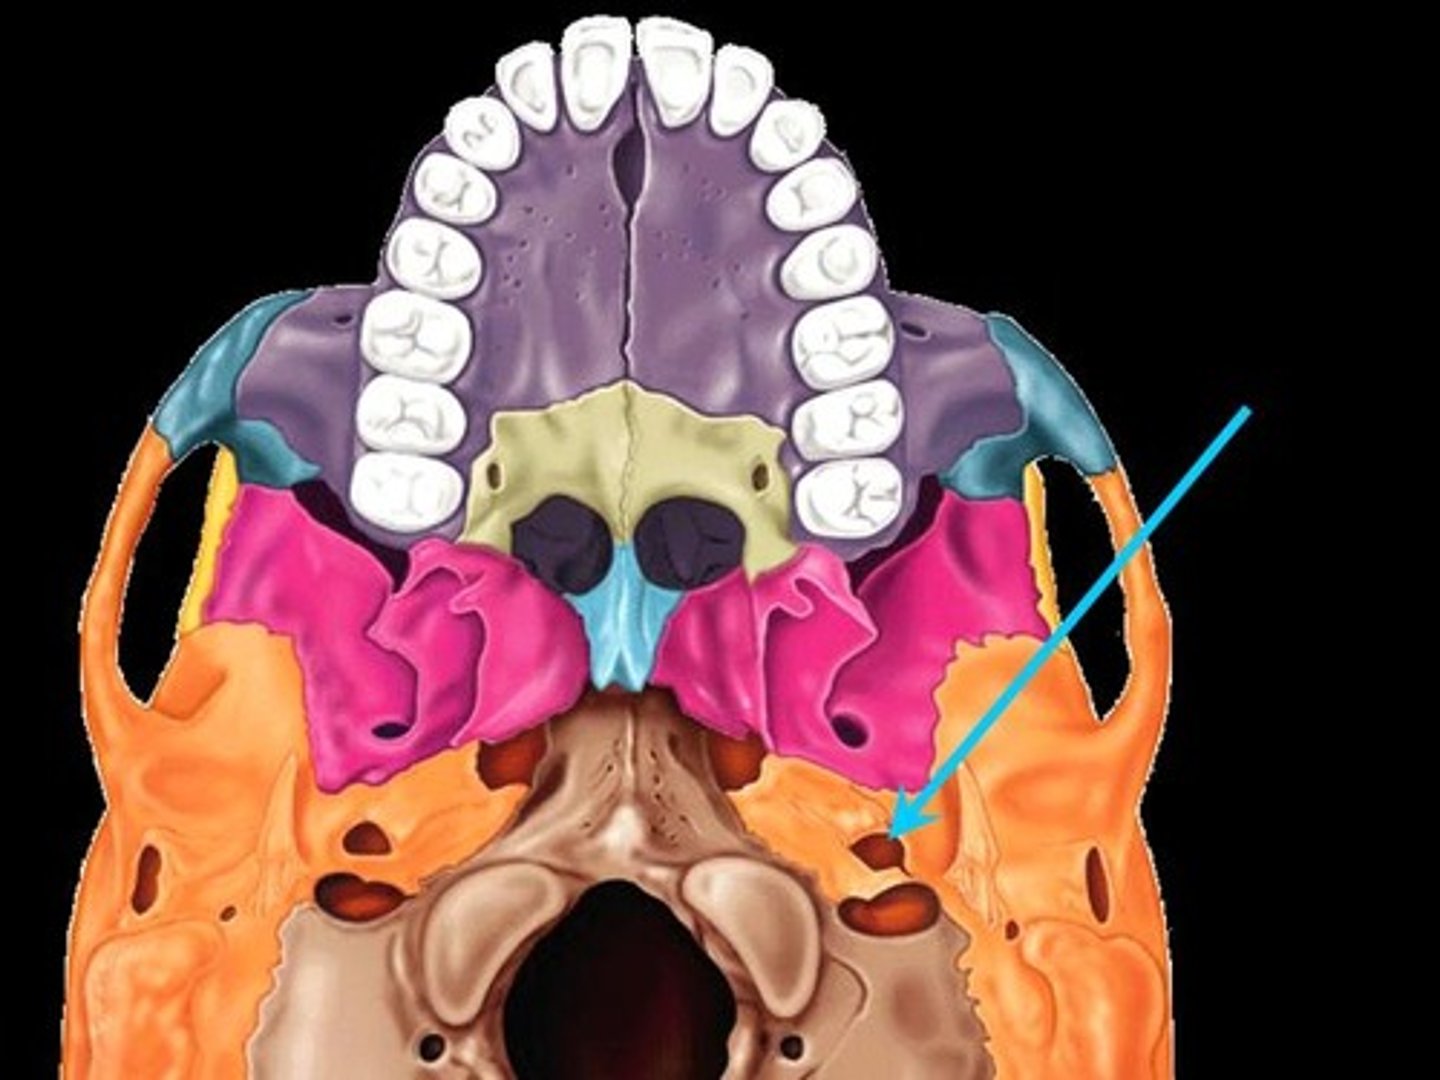

Foramen Lacerum

A triangular hole in the base of the skull located between the sphenoid, apex of petrous temporal and basilar part of occipital

Jugular Foramen

CN IX, X, XI, superior bulb of internal jugular, inferior petrosal and sigmoid sunuses, meningeal branches of ascending pharyngeal and occipital arteries pass through

Occipital Condyles

Rounded projections lateral to the foramen magnum that articulate with the first cervical vertebra (atlas)

Carotid Canal

The passageway in the temporal bone through which the internal carotid artery enters the middle cranial fossa from the neck

Mandibular Fossa

The depression in the temporal bone into which the condyle of the mandible fits